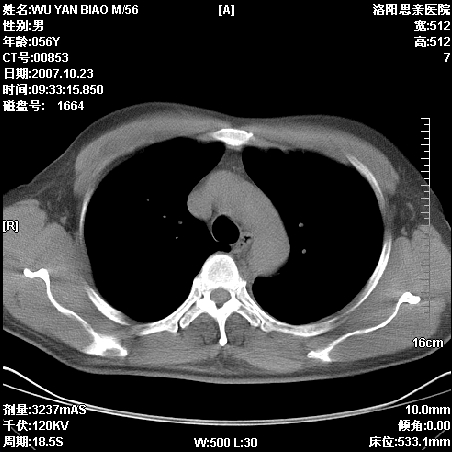

标题: CT10160:M56Y,体检发现,病人无不适,病人随访中 [打印本页]

标题: CT10160:M56Y,体检发现,病人无不适,病人随访中

后上纵隔占位,与肺交界清,宽基底附着脊柱,密度均匀,局部骨质无明确改变.

考虑;神经源性肿瘤,---起源交感n链?,不除外肠源性囊肿.

与纵隔关系密切,密度均匀。只能考虑:后纵隔神经原性肿瘤!

1、病灶在后纵隔脊柱旁沟内,此处是神经原性肿瘤的好发部位

2、病灶边缘光滑整齐,更说明病灶来于纵隔,由于有胸膜的包裹所以才导致这么光滑的边缘

3、病灶内的密度均匀